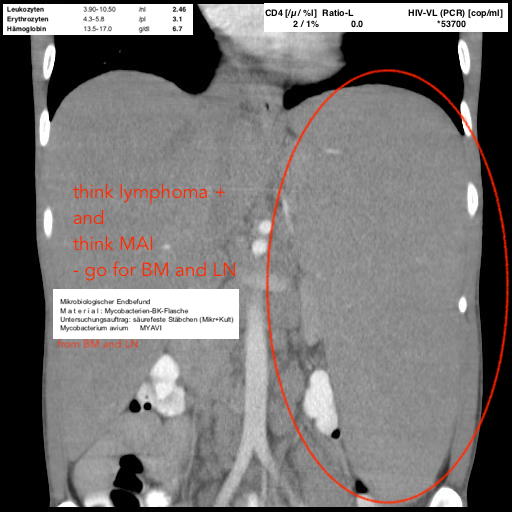

splenomegaly